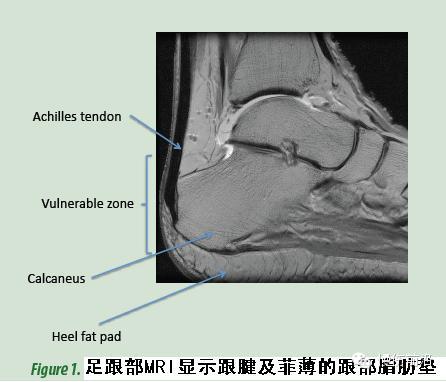

对足和足跟的评估,尤其是对高危患者,临床专家需要考虑卧姿、坐姿、站姿、移动、步态和局部压力与鞋子之间的相互作用。对每个患者的初步评估既要包含跟部压疮发生的特定风险因素(见前述文章),也要对患者进行整体评估,例如Braden和Waterlow评分。跟部后侧和外侧缺乏缓冲组织的保护(足跟部皮肤和骨头之间的厚度仅为3.8mm),压疮发生的风险极高(见图1和2)。